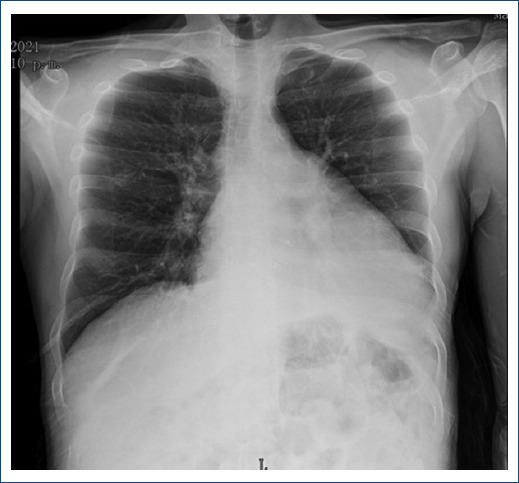

La telerradiografía del tórax mostro una cardiomegalia grado II-III con datos de hipertensión veno-capilar pulmonar y derrame en la pleura izquierda (Fig. 4).

Figura 4 Telerradiografía postero-anterior de tórax con presencia de cardiomegalia grado II-III con datos de hipertensión veno-capilar pulmonar y derrame pleural izquierdo.